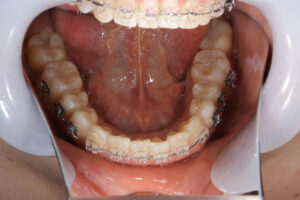

初診時に前歯が噛んでいない

初診時に奥歯が噛んでいない